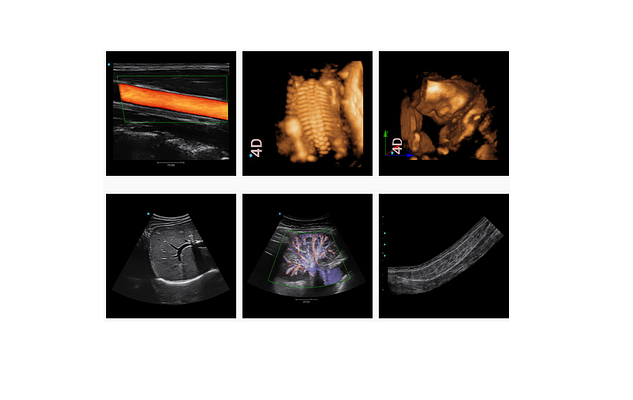

Máy siêu âm SIUI Apogee 5300 tích hợp nhiều công nghệ hàng đầu:

- Aotu OB: Tự động tính toán và đo đạc các chỉ số thai nhi, giúp tiết kiệm thời gian cho bác sĩ.

- XBeam: Cải thiện chất lượng hình ảnh siêu âm, tăng tỷ lệ khung hình trong chế độ B và 4D.

- Nanoview: Giảm tiếng ồn và cải thiện độ phân giải tương phản, giúp xác định sớm các tổn thương.

- Stress Echo: Chẩn đoán bệnh tim mạch vành và đánh giá chức năng dự trữ mạch vành một cách chính xác.

Các công nghệ này, cùng với TDI, Vis-Needle, FusionFreq, và nhiều tính năng khác, đưa Apogee 5300 lên hàng ngũ thiết bị y tế cao cấp, giúp các chuyên gia y tế chẩn đoán chính xác và hiệu quả.

Máy siêu âm SIUI Apogee 5300 không chỉ dừng lại ở việc chẩn đoán các bệnh lý tim mạch mà còn mở rộng ứng dụng trong nhiều lĩnh vực khác như sản khoa, bệnh lý tuyến vú, và hỗ trợ các thủ thuật can thiệp.

Với Stress Echo và TDI, máy cung cấp thông tin quý giá về chức năng và vận động cơ tim, giúp phát hiện sớm các bệnh lý tim mạch.

Aotu OB và các công nghệ hình ảnh 4D giúp theo dõi sức khỏe của mẹ và bé một cách chính xác nhất.

Vis-Needle nâng cao độ an toàn và chính xác trong các thủ thuật can thiệp, bao gồm sinh thiết và tiêm truyền.

Với công nghệ Elastography tiên tiến, SIUI Apogee 5300 giúp các bác sĩ chẩn đoán sớm ung thư vú bằng cách đánh giá độ cứng của mô. Kỹ thuật này tăng cường khả năng phát hiện sớm các tổn thương tiềm ẩn, giúp việc điều trị trở nên kịp thời và hiệu quả hơn.

Panoscope, một tính năng độc quyền của SIUI Apogee 5300, cho phép bác sĩ quét một diện tích lớn hơn, tạo ra hình ảnh toàn cảnh của khu vực quan sát. Tính năng này giúp bác sĩ có cái nhìn tổng quan hơn về cơ thể bệnh nhân, từ đó chẩn đoán chính xác và hiệu quả hơn.

- Chất Lượng Hình Ảnh Sắc Nét: Công nghệ 5D màu và các tính năng như Nanoview, XBeam, và Fusion THI mang lại hình ảnh siêu âm rõ ràng và chính xác.